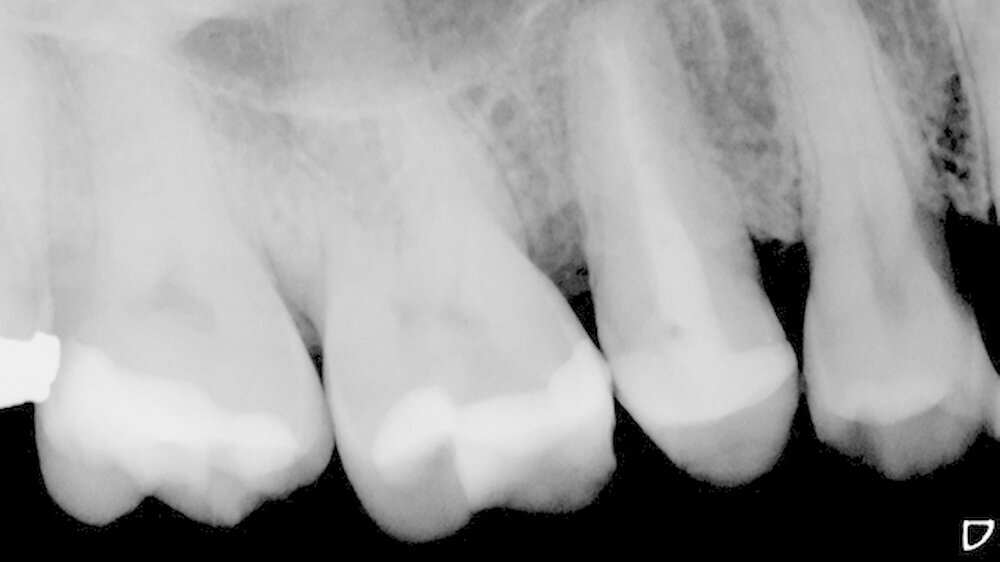

In der Poliklinik für Zahnerhaltung des Universitätsklinikums Münster war zwar die allgemeinmedizinische Anamnese unauffällig, doch zeigte sich klinisch nach Entfernung der vorhandenen mod-Glasionomerzementfüllung ein deutlicher Frakturspalt in mesial-distaler Ausrichtung am Boden der Kavität (Abbildung 1). Darüber hinaus war auf der Röntgenaufnahme des Vorbehandlers eine apikale Aufhellung zu erkennen (Abbildung 2).